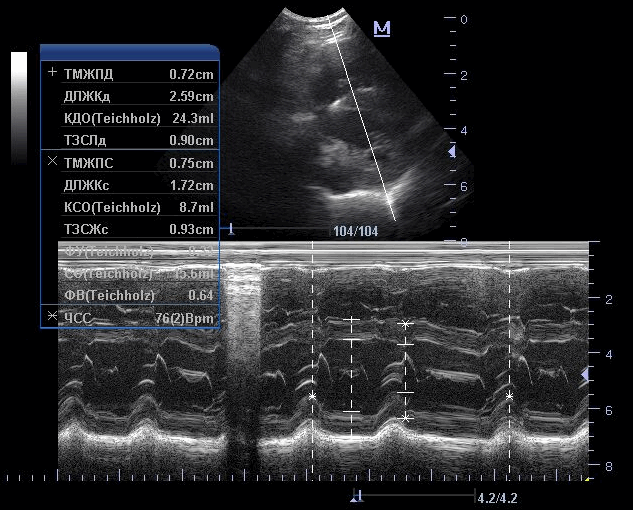

2. М-режим - графическое изображение движения стенок сердца и створок клапанов во времени. М-режим позволил впервые в реальном времени оценить размеры сердца и систолическую функцию желудочков. В настоящее время применяется как вспомогательный режим при проведении эхокардиографического исследования преимущественно для измерений.

Рис.3. Эхокардиография. М-режим. Измерения параметров